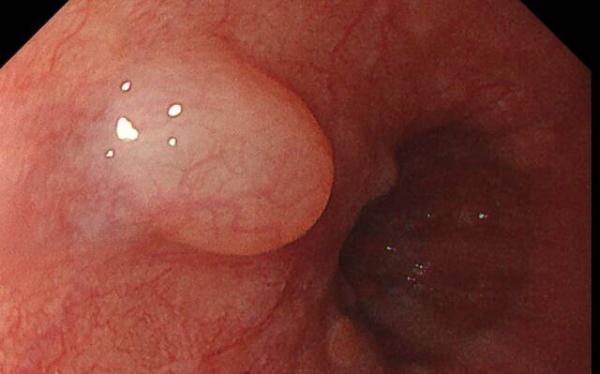

以下情况几乎都会取活检,但不代表病情严重,而是出于诊断需要:

◯ 可疑溃疡或不规则糜烂

◯ 黏膜颜色改变(发红、苍白)

◯ 黏膜形态异常(隆起、凹陷、息肉)

◯ 萎缩性胃炎或肠上皮化生

◯ 息肉样病变

报告常见术语

在奥林巴斯X1设备及高清放大内镜的支持下,新镜界全面采用“精准取活检”技术。

在检查过程中,若发现高度怀疑早癌或诊断不明确的病灶,及时与患者家属沟通,经同意后,进行精准靶向活检。避免对典型良性病变或计划行诊断性ESD/EMR的浅表癌进行活检。

运用奥林巴斯X1设备及高清放大内镜,针对可疑区域精准取样,检出率大幅提升。